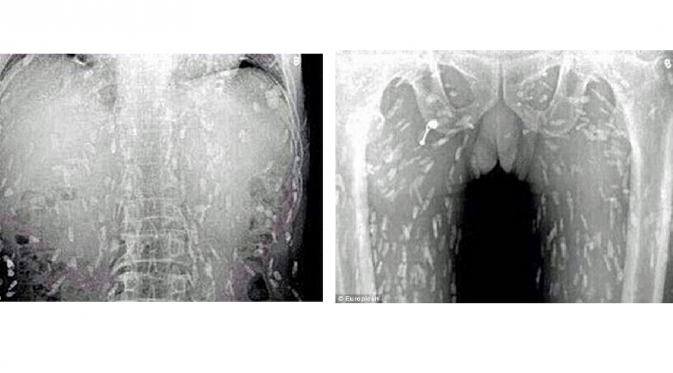

Dokter yang melakukan pemindaian pada tubuh pasien, menemukan kodisi horor: cacing pita memenuhi badan pria tersebut setelah ia kebanyakan makan sashimi -- makanan ala Jepang berupa irisan daging ikan mentah.

Dokter yakin, ikan mentah yang dikonsumsi penderita telah terkontaminasi. Pasien akhirnya dirawat di Guangzhou No. 8, Rumah Sakit Rakyat di Provinsi Guandong di China timur.

Sementara, Dr Yin dari Rumah Sakit Guangzhou No. 8 dalam situs that'smags.com mengatakan bahwa makanan yang terkontaminasi telur cacing pita bisa menyebabkan cysticercosis -- kondisi ketika cacing dewasa masuk ke aliran darah seseorang.

Tipe infeksi ini tak bisa dianggap remeh. Bisa mengancam jiwa seseorang, jika cacing mencapai otak manusia.